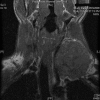

Case presentation: A 27 year male presented with a gradually enlarging, asymptomatic swelling on left supraclavicular region with normal overlying skin. A soft mass, about 7 x 7 cm with restricted mobility was found with normal cranial nerve function. Fine needle aspiration cytology showed a hemorrhagic aspirate. Doppler showed a mass displacing left carotid artery posteriorly while left internal jugular vein was not visualized. Magnetic resonance imaging showed a well defined mass isointense to hypointense on T1 weighted and hyperintense on T2 weighted and STIR images with fluid-fluid levels. On exploration, a vascular mass arising from left internal jugular vein was found with good tissue planes, which was excised after ligating the patent internal jugular vein above and below the lesion. Histopathologic examination confirmed the diagnosis of vascular malformation.